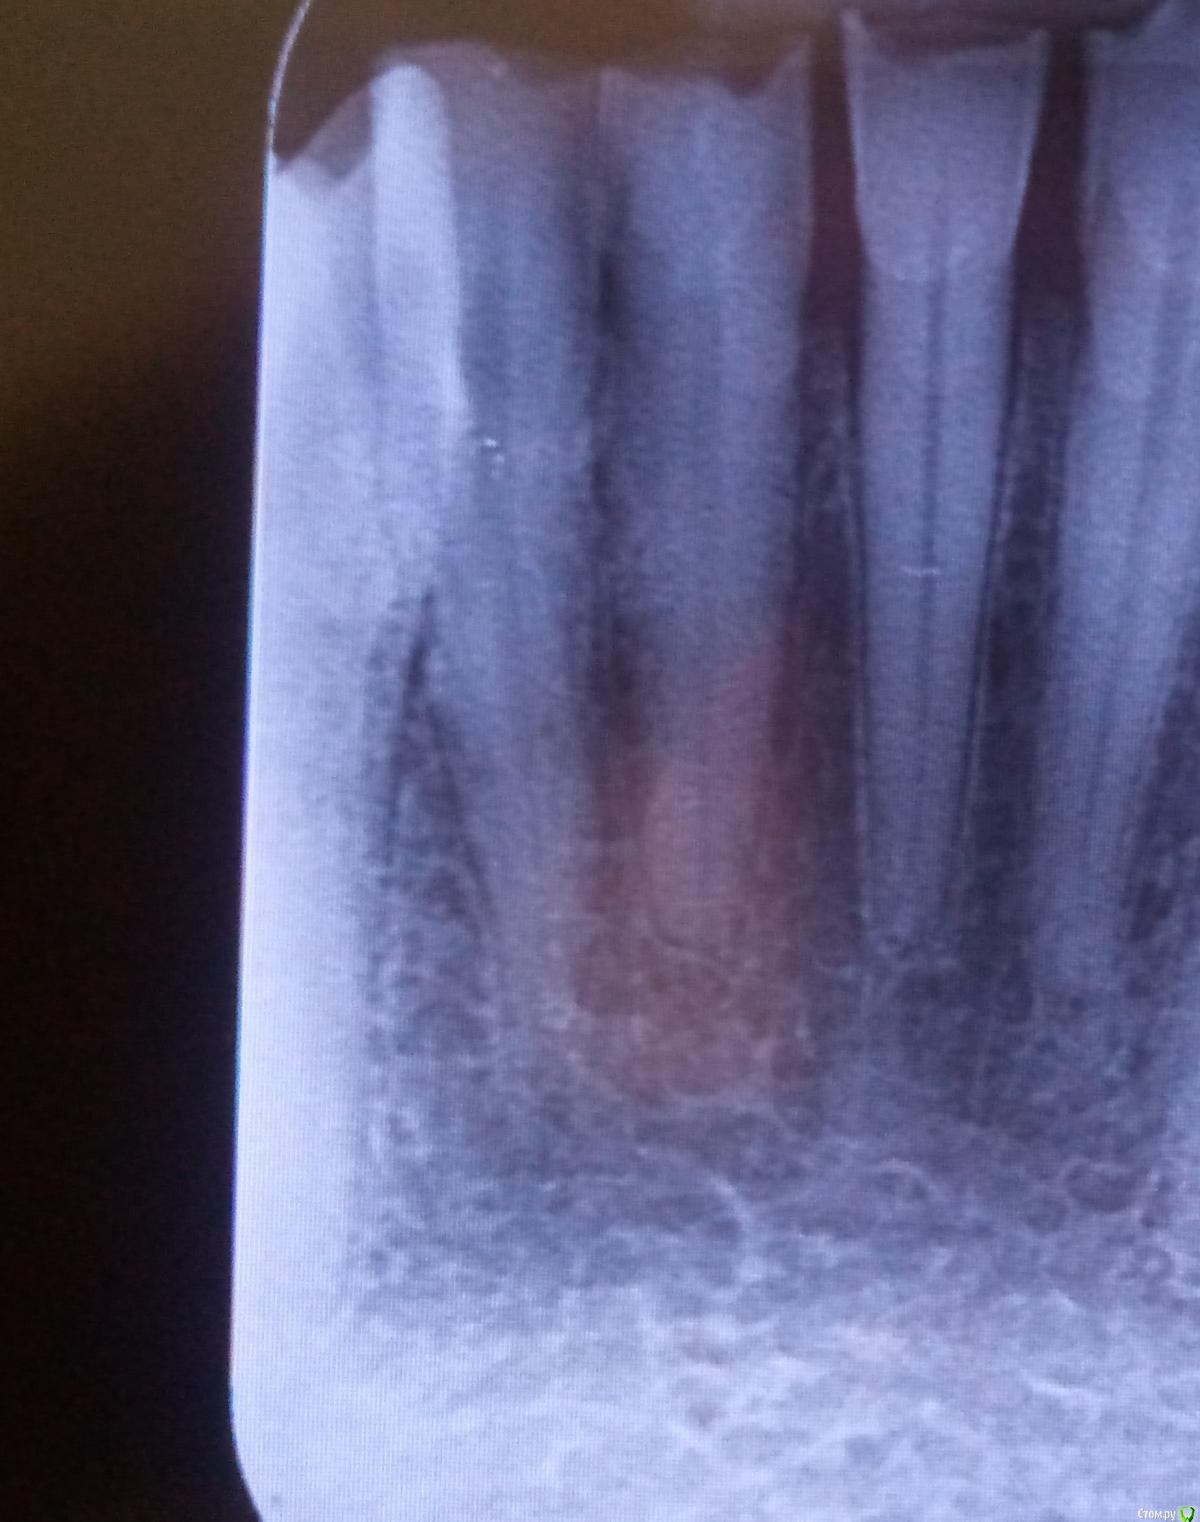

Studentic Опубликовано 7 июня, 2018 Автор Поделиться Опубликовано 7 июня, 2018 К моему большому сожалению, из-за неопытности разбил перешеек между разветвлениями. Пломбировал гуттаперчевыми штифтами, из силлеров имел только дексодент. Как вы думаете, какой прогноз на ближайшее время, учитывая что у верхушечной трети штифты следовало укомпактовать получше? Ссылка на комментарий

St. Опубликовано 7 июня, 2018 Поделиться Опубликовано 7 июня, 2018 По снимку немножко перестарались, но учитывая что зуб был витальный все должно быть хорошо. Могут быть постпломбировочные боли. Ссылка на комментарий